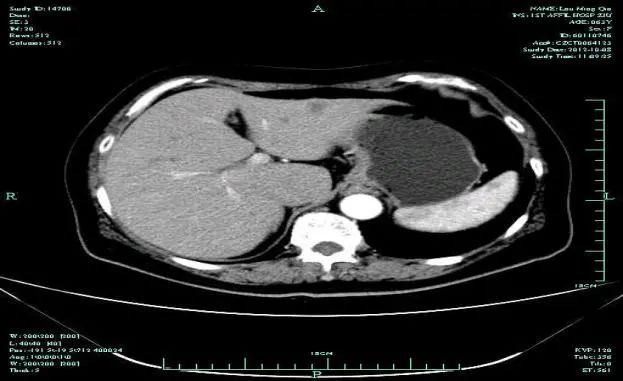

影像学表现:

• CT示:肝转移

CT-T

CT-H1

影像学检查结果评估:cPD。